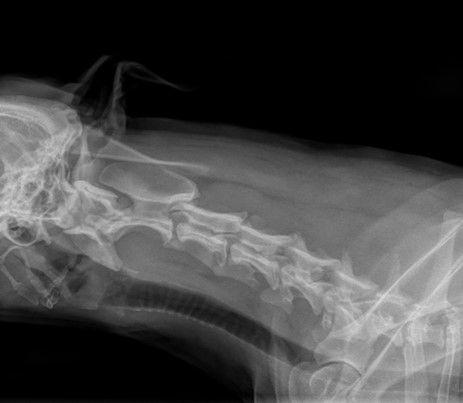

Sehr kompetenter Tierarzt den ich nur weiterempfehlen kann. Ich komme aus Marl das sind bis Witten 36km/31min mit dem Auto aber das ist es mir wert 🤓 Er nimmt sich die Zeit für meinen Hund und ist fachlich und menschlich Super 👍🏼Wir kennen Herrn Tenhaven seit 2020 aus der Tierklinik in Recklinghausen. Damals konnte er nur meinem Labrador Rüden Luke helfen. Er hatte seit längeren eine Ohrentzündung gehabt. Unser letzter Tierarzt hat immer nur Ohrreiniger aufgeschrieben aber nicht nach dem Grund gesucht weshalb es so ist!? Kurz entschlossen beschloss ich mir einen Termin in der Tierklinik in Recklinghausen mir geben zu lassen. Herr Tenhaven hat direkt nach dem Grund der Ohrentzündung gesucht und hatte eine Probe aus dem Ohr genommen. Nach mikroskopischer Untersuchung wurden Hefepilze nachgewiesen. Es folgte eine Futterumstellung mit Pferd. Seitdem ist das Ohr wieder super 👍🏼👍🏼👍🏼 Die Arthrose in der Schulter hatte Herr Tenhaven auch festgestellt 🥳selbst das wurde nicht vom Haustierarzt festgestellt und wollte nur Tabletten aufschreiben. Ich wollte gerne die Ursache herausfinden weshalb mein Hund humpelte. Herr Tenhaven ist einfach Super. 💪🏼 Wir kommen gerne wieder 😇